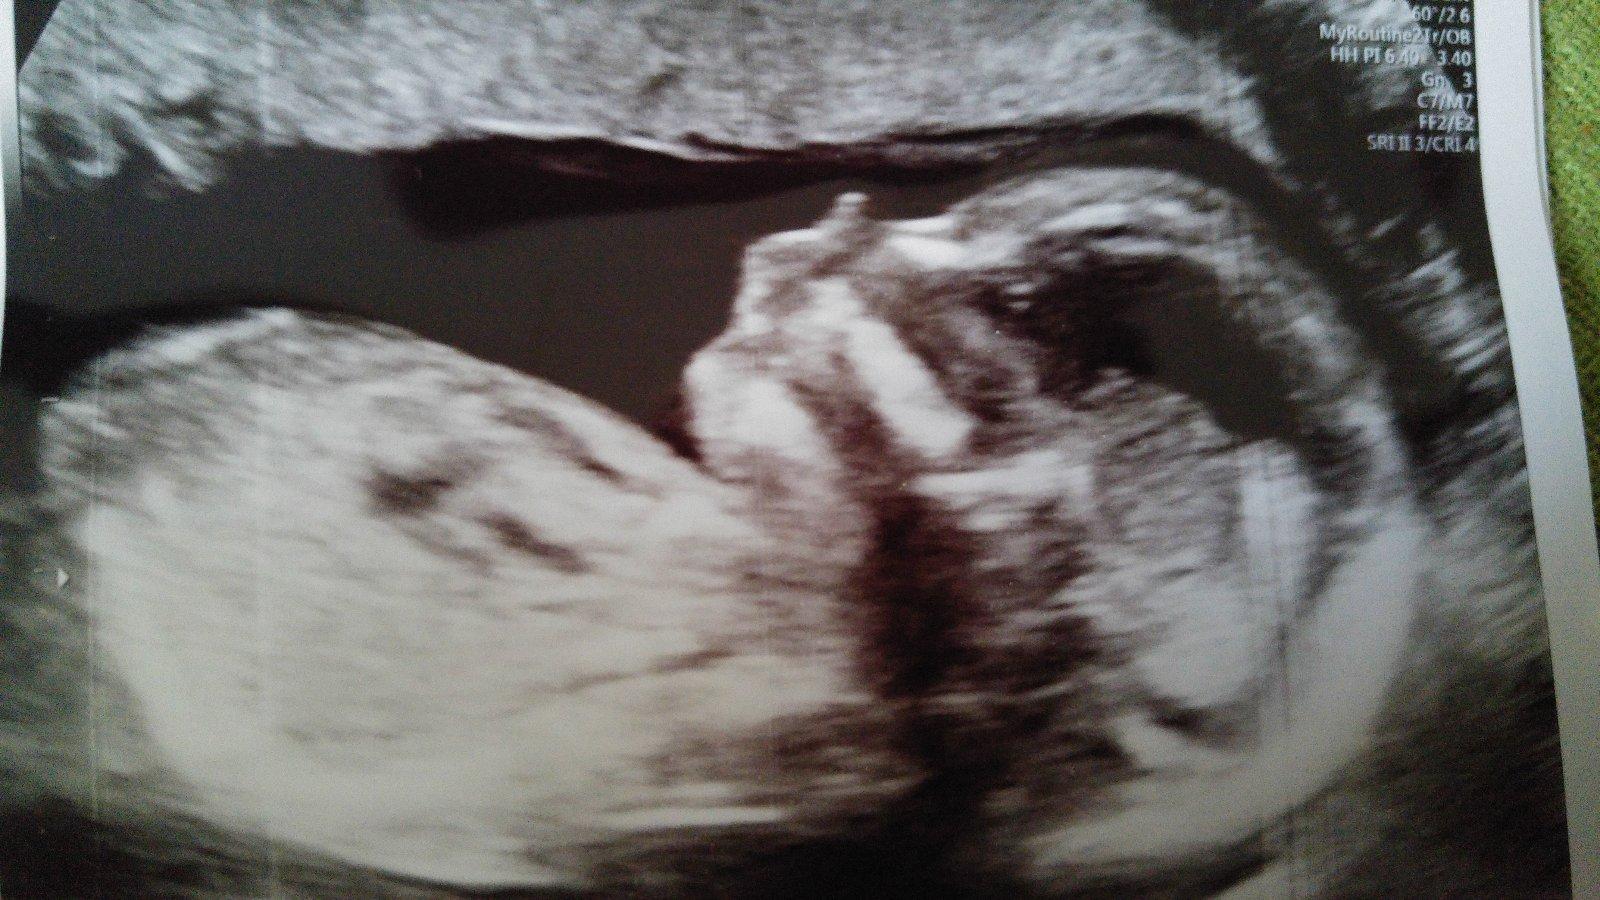

Tu je ❤❤❤

Naš pokladík 🙂 na 2 fotke vidieť pinďulíka 🙂